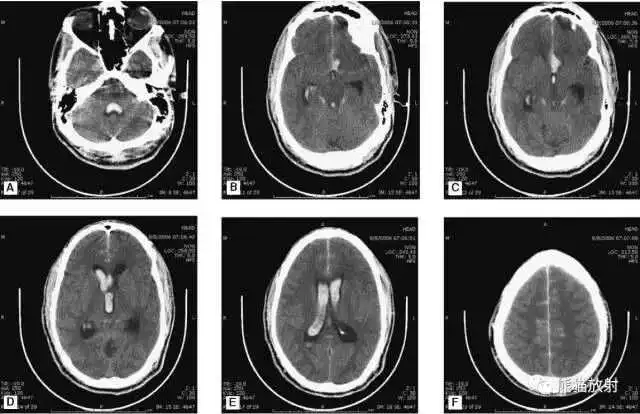

动脉瘤破裂导致蛛网膜下腔出血、

脑室积血、非交通性脑积水。

与外伤性蛛网膜下腔出血不同,动脉瘤破裂导致的SAH常不累及大脑凸面,而位于基底池附近。脑动脉瘤常位于鞍上池的Willis环血管。

A:四脑室积血;

B:中脑导水管、环池、右侧侧脑室颞角积血,前交通动脉处(动脉瘤好发位置)出血密度较高;

C:三脑室积血;

D-F:侧脑室积血,蛛网膜下腔出血(血液代替了脑脊液)。